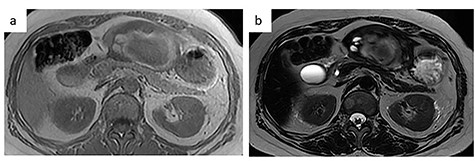

MRI. (a) T1-weighted image: low-intensity area suggestive of intratumor hemorrhage. (b) T2-weighted image: the tumor had heterogenous intensity.

In the present case, contrast-enhanced CT demonstrated two-layered enhancement of the liver tumor. Considering the gross findings of the liver tumor, the inner layer consisted of a hematoma, and the outer layer was formed by compression of the tumor into a crescent shape by the intratumor hematoma, as seen on MRI. Since thymomas, including those that metastasize to the liver are soft, they can rupture easily and can be easily compressed by intratumor hematoma.